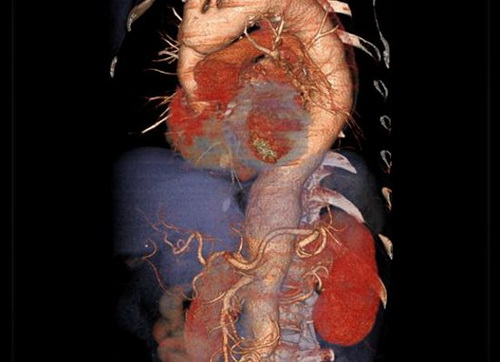

制作有用的医学图像涉及两个主要步骤:一是搜集数据,二是将这些数据转换为可快速、准确解读的图像。这张图像由一种称为X射线断层成像(简称CT)的先进X光技术生成,突出了上述两个方面的进步。体绘制软件(Volume-rendering software)结合CT血管成像技术,可以识别心脏附近主动脉(从图像顶端延伸至身体下部、心脏周围的大片粉色血管)的异常情况。再往下,可以清楚看到肝脏(紫色)和肾脏(鲜红色)。准确测定主动脉直径至关重要,因为外科医生可以借此判断主动脉是否存在破裂的风险。